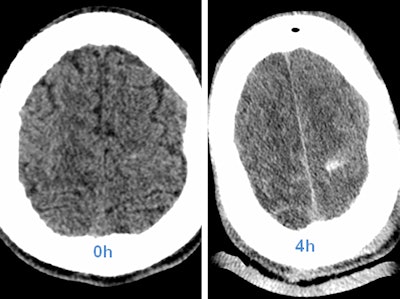

Above: CT head scan with increasing visibility of intracranial hemorrhage in the first few hours. Left: Unenhanced head CT; bleeding is hard to depict. Right: Control scan four hours after whole-body CT, and thus after contrast enhancement. Below: Images show traumatic rupture of the bowel. Images courtesy of Dr. Stefan Wirth.Radiologists also need to include treatment planning with the surgeon and anesthetist when optimizing processes in polytrauma management.

However, very early stages of bleeding, especially in the brain, may be hard to detect, he cautions. Radiologists should be aware of possible hyperacute intracranial bleeding without tremendous density above the surrounding parenchyma.

"If in doubt, repeat the scan. In most cases when a second scan seems appropriate, limiting the procedure to particular organs is sufficient," he said.